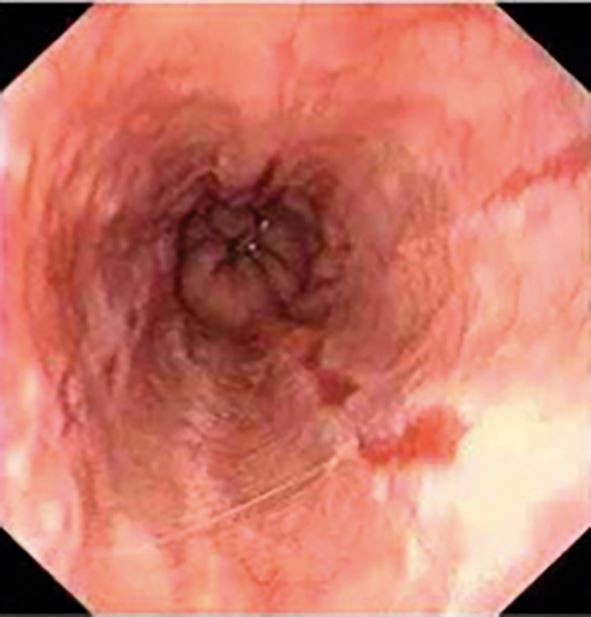

Diagnosis is often clinical; however, upper endoscopy is warranted for red flag symptoms, or no improvement after eight weeks of medical treatment. The role of endoscopy is to confirm diagnosis (erosion/ulcerations or non-erosive reflux disease), exclude atypical causes (eosinophilic esophagitis, candida, herpes simplex) and diagnose complications (Barrett's oesophagus, stricture, adenocarcinoma) (Fig. 6, Fig. 7, Fig. 8).